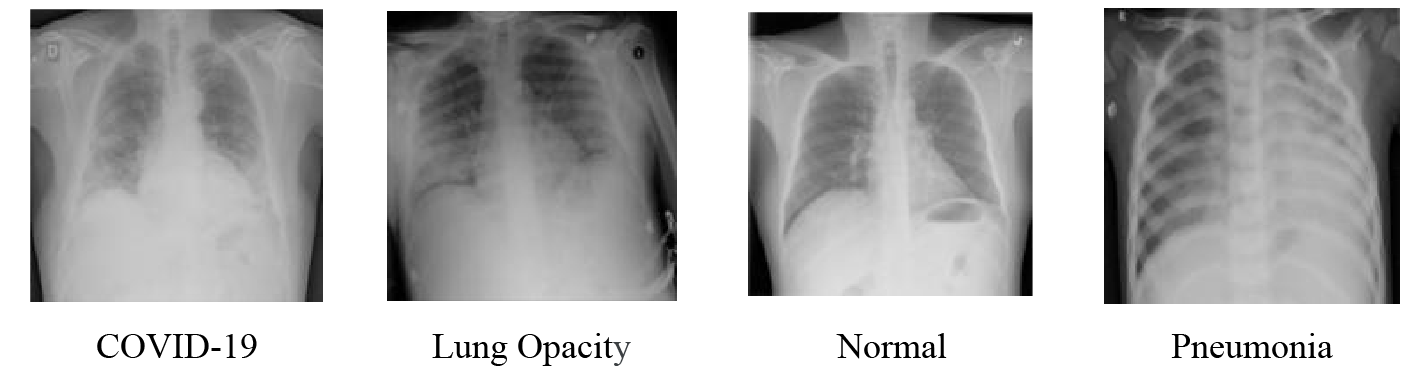

The dataset uses in this paper is a publicly available dataset from the COVID-19 RADIOGRAPHY DATABASE, created by a team of researchers from Qatar University and Dhaka University in Bangladesh, along with collaborators from Pakistan and Malaysia, in collaboration with physicians [22,23]. A total of 5374 medical images are selected, including 1332 images of COVID-19, 1335 images of lung opacity, 1362 images of normal lung and 1345 images of viral pneumonia. The images are shown in Fig. 6. The ratio of 9:1 is divided into the training set and the verification set. In order to match the model input size, the image is randomly cropped to 224 × 224, then it is converted to vector format and the pixel value is normalized.

Figure 6: Lung X-ray image samples